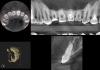

Hoderkov Опубликовано 21 августа, 2013 Поделиться Опубликовано 21 августа, 2013 (изменено) Последствия падения.Зуб 1.1 не болит, слегка отбит верх коронки, можно сохранить? Извините, пишу одной левой рукой Изменено 21 августа, 2013 пользователем Hoderkov Ссылка на комментарий

kriokov Опубликовано 21 августа, 2013 Поделиться Опубликовано 21 августа, 2013 Последствия падения.Зуб 1.1 не болит, слегка отбит верх коронки, можно сохранить? по снимку неполный вывих, и кортикальная вестибулярная треснула. Корень целый. По моему можно сохранить Ссылка на комментарий

Adrenalin Опубликовано 23 августа, 2013 Поделиться Опубликовано 23 августа, 2013 Фиксировать и наблюдать - должен прижиться! Ссылка на комментарий